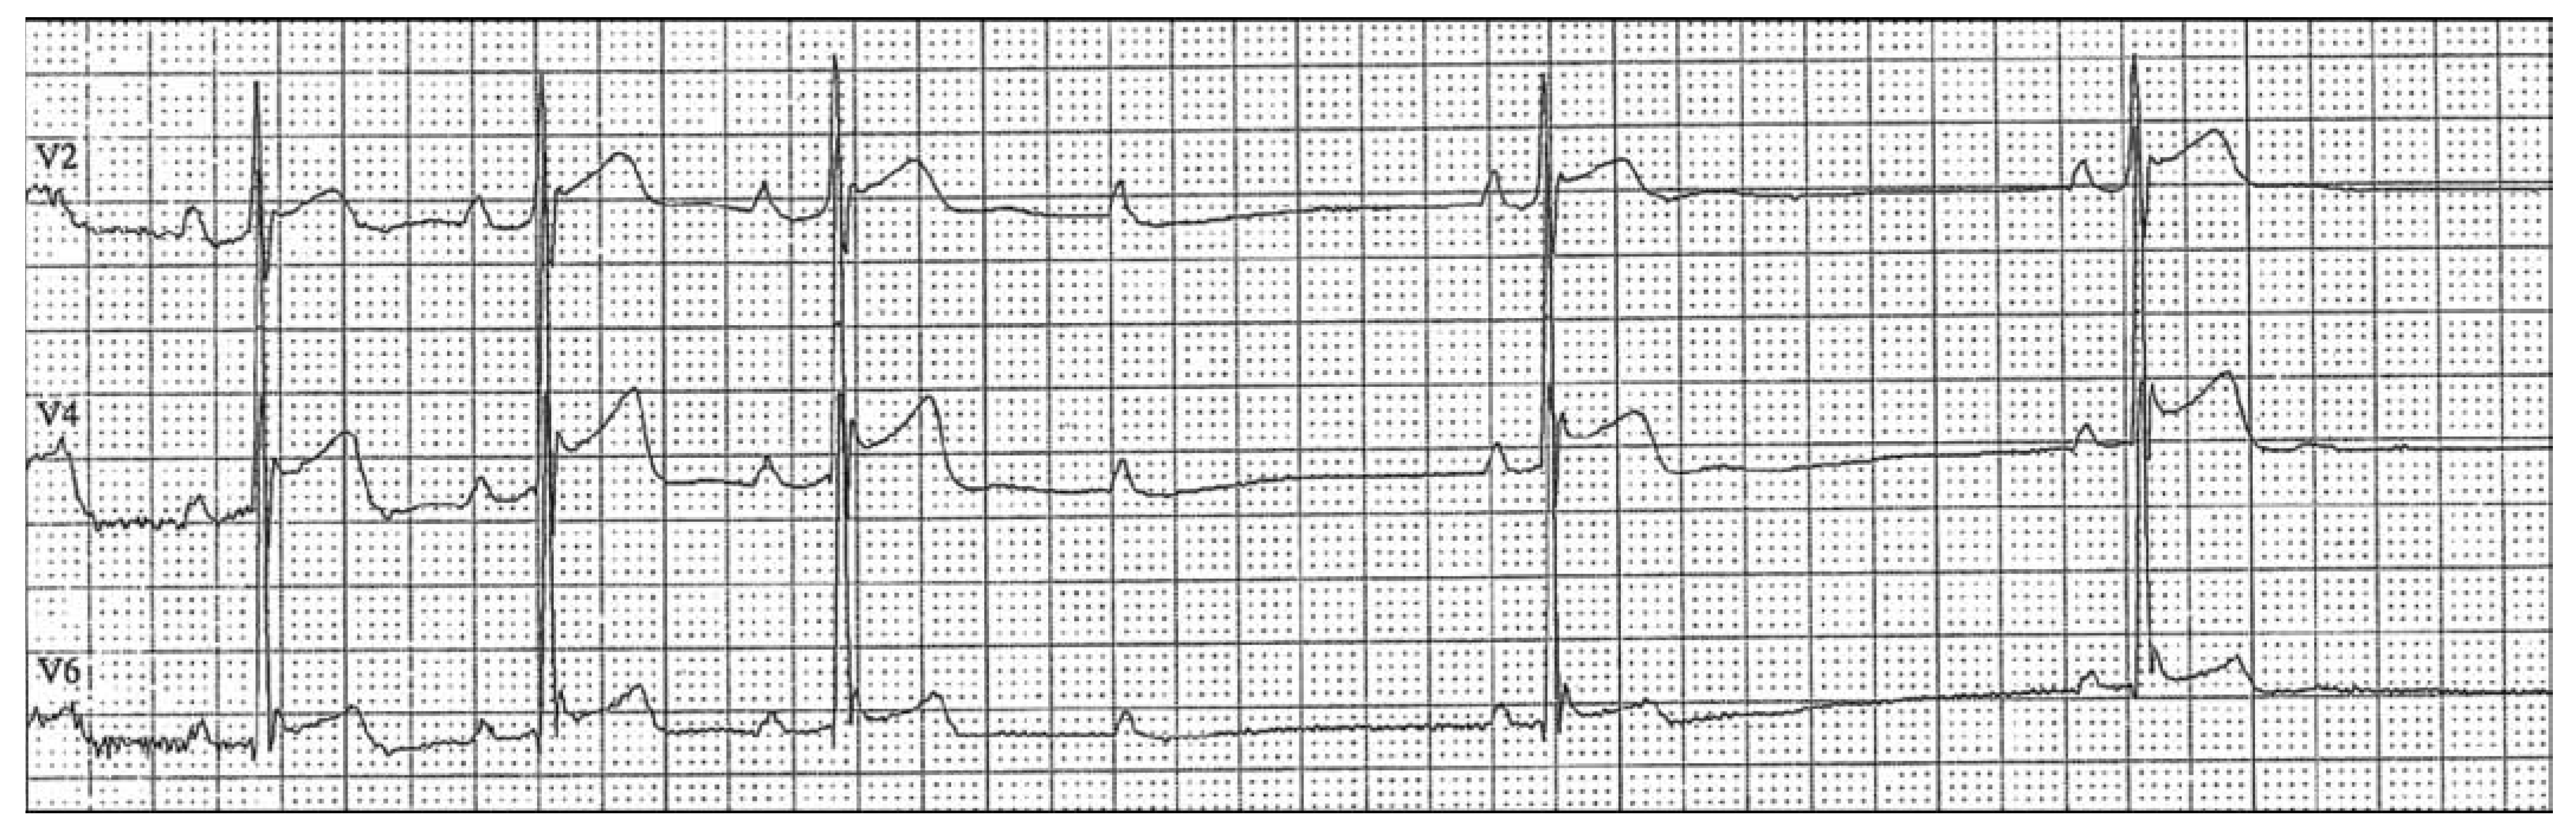

Second Degree Atrioventricular Block: Type I or Type II?

Case Report

Explanatory answers